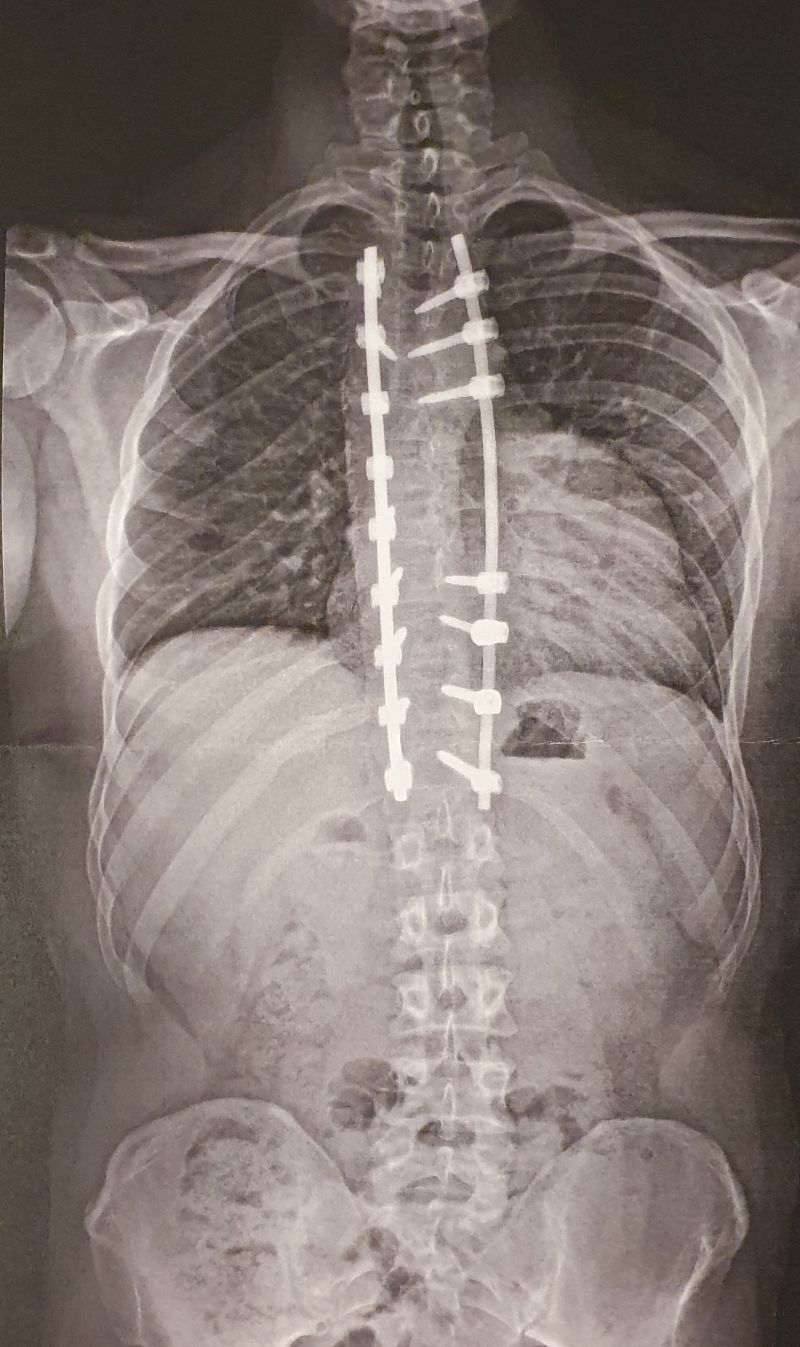

Die OP fand Anfang März statt. Es wurde von Th4 bis Th12 versteift und auf 7° und 9° korrigiert. Die Rotationskomponente konnte ebenfalls sehr gut korrigiert werden, sodass ich zum ersten Mal in meinem Leben ein halbwegs symmetrisches Skelett habe. Ferner wurde sehr sorgsam auf mein sagittales Profil geachtet, wodurch ich von einem Fast-Flachrücken nun auf einen Kyphosewinkel von 25° komme.

Die Fotos zeigen meinen aktuellen Zustand. Es ist leider so, dass ich trotz der recht geringen Krümmung von 45° eine deutliche Rippendeformität ausgebildet hatte, die auch nach der OP natürlich nicht weg ist. Man wird also immer eine gewisse Asymmetrie erkennen. Im Vergleich zum Zustand vor der OP liegen jedoch Welten.